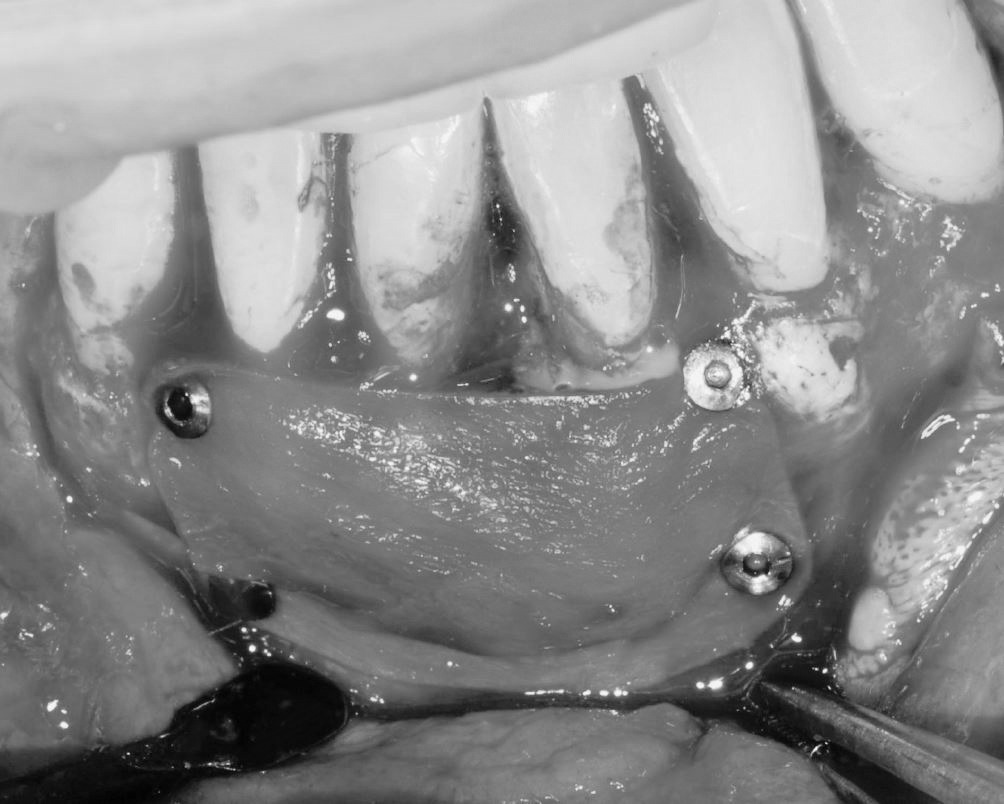

Objetivos periodontales: Regeneración osea guiada con bioss collagen y emdogain.

- Eliminar tejido necrótico. Regeneración periodontal cemento, ligamento y hueso

- Mejora de la estabilidad y soporte óseo

- Estabilidad periodontal y reducción de la movilidad

Profilaxis mediante airflow y descontaminación periodontal. Más ferulización periodontal

R.A.R. Profundo suave intraquirúrgico

Aplicación protocolo emdogain

Regeneración ósea guiada con membrana de colageno creos de Nobel Biocare y relleno óseo mediante BIOSS Collagene de INIBSA, con elementos de fijación a la membrana para R.O.G.

Fotografías del proceso: